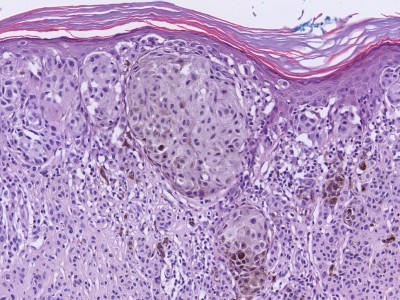

PA:Ook histologisch is het

superficial

spreading melanoom de meest voorkomende variant. Hierbij zijn de nesten van

atypische melanocyten gelegen in een band onder de epidermis. Er is

hoofdzakelijk groei in horizontale richting. Soms is er plaatselijk een

verticale groeifase, met invasie in de diepte of juist exofytische groei

zoals bij een

nodulair melanoom. Een andere veel voorkomende variant is het

PA superficial

spreading melanoom:De epidermis bevat een groot deel van de primaire laesie. Men ziet hier een Pagetoïde verdeling van de maligne melanocyten. Vaak ziet men nestjes cellen intra-epidermaal. Grote melanoomcellen kunnen zich tot in de oppervlakte van de epidermis, soms zelfs tot in het stratum corneum bevinden, solitaire zowel als omschreven groepjes. Ook kunnen ze vrijwel de gehele epidermispopulatie vervangen. De meeste intra-epidermale cellen zijn van het epitheloide type met fijnkorrelig pigment in het cytoplasma. De kernen zijn irregulair en hebben één of meer nucleoli. Mitosen komen voor, maar niet frequent. Er is een grotere monomorfie van de intra-epidermale melanoomcellen dan bij

lentigo maligna melanoma het geval is. Zolang het melanoom nog intra-epidermaal is, is er vrijwel geen ontstekings infiltraat in de cutis. Invasie van de cutis (stadium II) toont hetzelfde celtype als intra-epidermaal. De cellen vormen een geheel met het intra-epidermale deel. Soms liggen zij in strengen, nesten of solitair. Steeds ziet men een dicht aspecifiek lymfohistiocytair infiltraat met mestcellen en plasmacellen en een aantal melanofagen. In stadium III neigen de cellen tot vorming van kleine nesten. Sommige nesten bevatten vrijwel geen pigment (amelanotisch melanoom). Vanaf stadium III (de grens van stratum papillaire-reticulaire) groeien celstrengen tussen de collageen bundels van het stratum reticulaire door, soms tot in de subcutis (stadium V). In dat geval is de epidermis meestal ulceratief en toont nog maar weinig intra-epidermale tumorcellen.